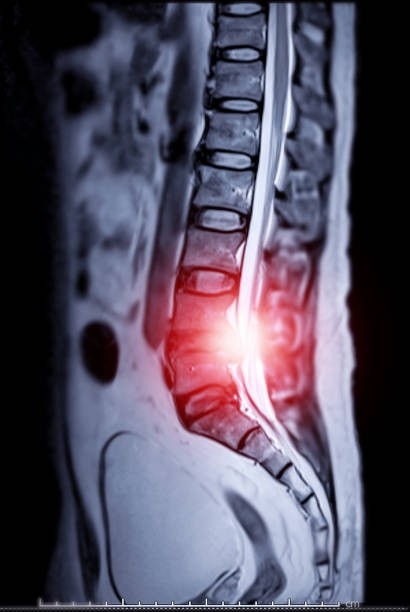

2. 영상 검사: MRI나 CT 스캔과 같은 영상 검사는 L4-L5 디스크 탈출증의 정확한 진단에 필수적입니다. 이러한 검사를 통해 디스크 탈출의 정도, 위치, 그리고 신경근 압박의 정도를 정확히 파악할 수 있습니다.

X-ray 검사는 척추의 전반적인 상태를 평가하는 데 도움이 될 수 있지만, 연부 조직인 디스크의 상태를 직접적으로 보여주지는 못합니다.